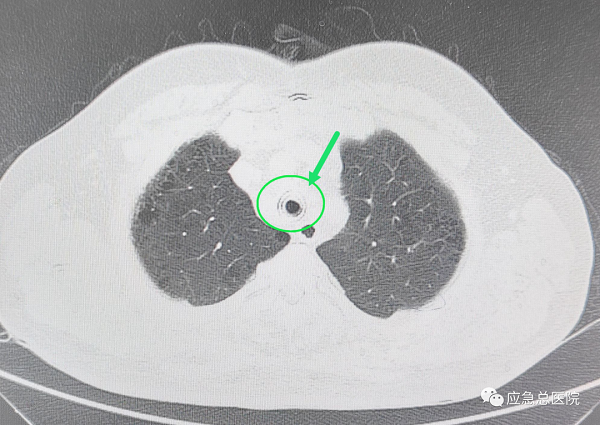

全身麻醉下,王洪武教授应用王氏插入法,仅5秒钟就成功插入硬质镜,建立了治疗和抢救通道,电子支气管镜下,可以看见原来的裸支架已经埋入气管粘膜内,突入的组织使得管腔仅有20%的空间能够流通空气,在张楠教授等专家的协助下,应用硬镜铲切、硬镜扩张、ND-YAG激光、高频电、氩气刀、二氧化碱冻取、球套扩张等多种技术配合,切除气管内增生的肉芽组织、部分异常粘膜,将原裸支架烧断、分解,抽丝剥茧,最后将整个支架完整取出,气管狭窄程度减轻为50%,手术结束后患者迅速苏醒,感到憋气症状明显缓解。

5天后,患者气管粘膜恢复,局部坏死物排出,再次气管镜局部治疗,清理管腔,经再次评估及精确测量后为患者放置了一枚气管硅酮支架,至此狭窄段管腔恢复至正常管径的80%,气喘症状完全缓解。患者激动地说:“能让王洪武教授这样的顶级专家亲自为我做手术,我太幸运了,是应急总医院给了我第二次生命啊!”